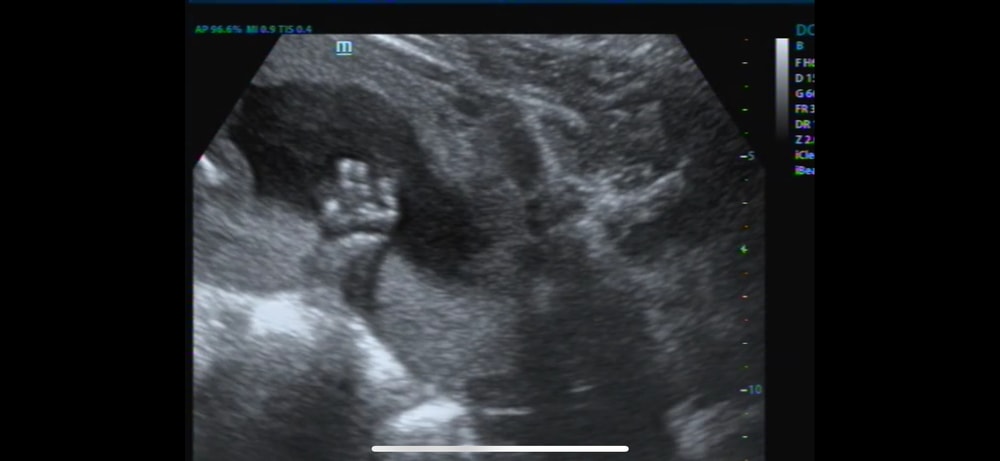

Все хорошо, срок 9+2 , развиваемся и уже шевелимся 🥰😍